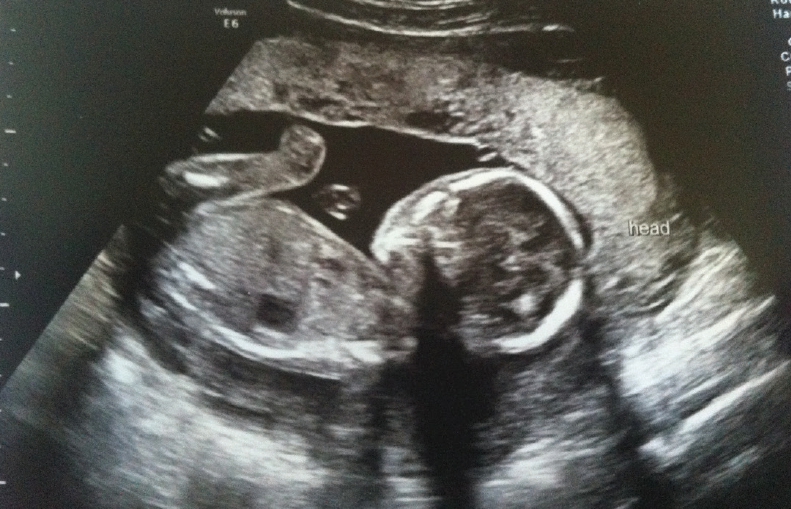

Vorbim despre anomaliile care se pot detecta prin ecografia fetală și în ce măsură se poate interveni în cursul sarcinii asupra unor asemenea malformații.

Sunt multe anomalii care pot fi diagnosticate intrauterin prin ecografia fetală, dar rata de depistare este departe de 100%. S-a pus foarte mare accent pe instruirea celor ce practică ecografia fetală, pentru a lucra la un nivel standardizat. Acest lucru se face prin ghidurile de examinare ecografică de trimestrul I și II, de pe site-ul Societății Române de Obstetrică și Ginecologie, dar și prin numeroase cursuri. Pot enumera câteva dintre situațiile fetale mai frecvent diagnosticate și pentru care se intervine cu rezultate de multe ori încurajatoare:

La ora actuală accesul la ecografia 3D/4D în țara noastră este relativ facil. Eforturile financiare ale sistemului medical privat și de stat, din ultimii 10-12 ani, au adus ecografe dotate cu aceste aplicații ale ultrasonografiei fetale, în cele mai multe locuri unde se monitorizează sarcini. Important este ca aceste sonografii volumetrice să fie precedate de cele morfologice.